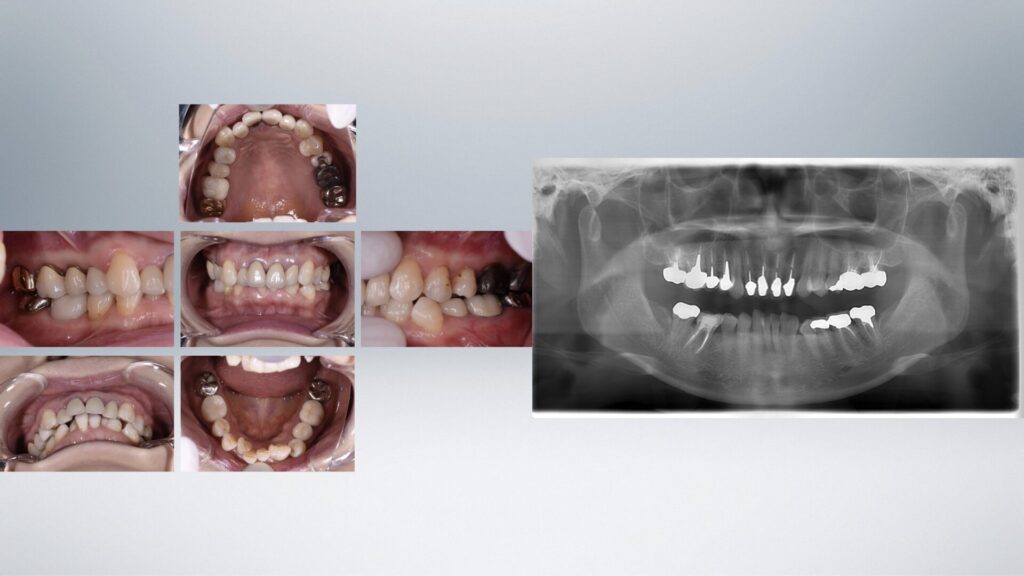

Before

| 主訴 | 将来に対する不安がある |

|---|---|

| 診断名 | 歯列不正(叢生)、歯牙の先天欠損および癒合歯 |

| 年齢・性別 | 50代女性 |

| 治療期間・回数 | 40ヶ月 |

| 治療方法 | 初診時に歯列不正を伴う多数の失活歯(神経がない歯)があり、将来的な歯牙破折による治療の複雑化が予測されました。各歯牙に問題が起こる前にマウスピース矯正により歯牙のポジションを整え、セラミック修復を行い将来的なリスクを軽減することに努めました。 |

| 費用 | 400万円 |

| 注意点 | 全顎的に治療が必要なため治療期間がかかります。治療の中には保険治療が含まれていない項目があるため費用がかかります。治療期間中は仮の歯で生活する必要があり、仮歯の破損や脱離が起こることがあります |

| 備考 |